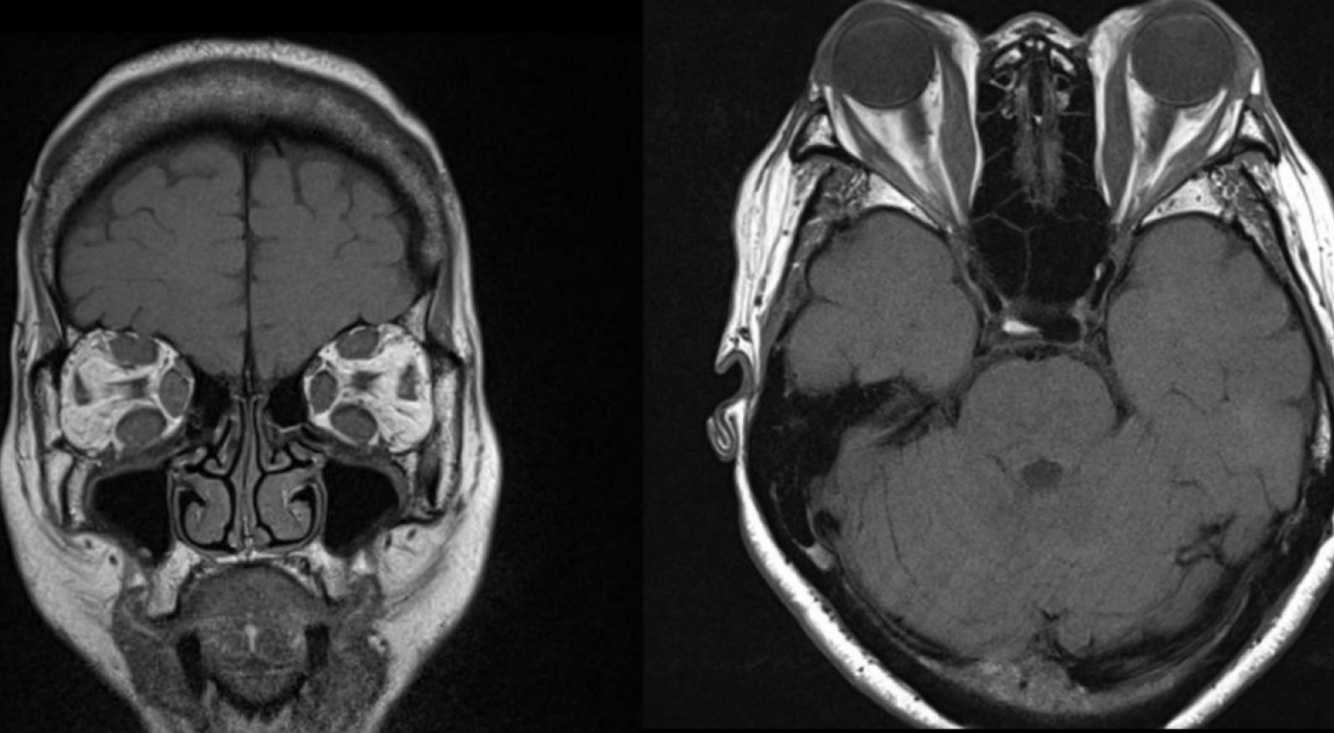

Q

Orbitopatía tiroidea

Hallazgos en T2:

A

Fases

• Aguda: aumenta señal en músculos

• Crónica: baja densidad

Diámetro disminuido en N. óptico

Hallazgos de TC de RB:

• Calcificación manchada o punteada

• Masa con densidad intermedia

• Capta contraste

14

Hallazgos en RM:

• Evaluar implicaciones intra y extraoculares

• Hemorragia

• Mejor caracterización de lesión en pineal